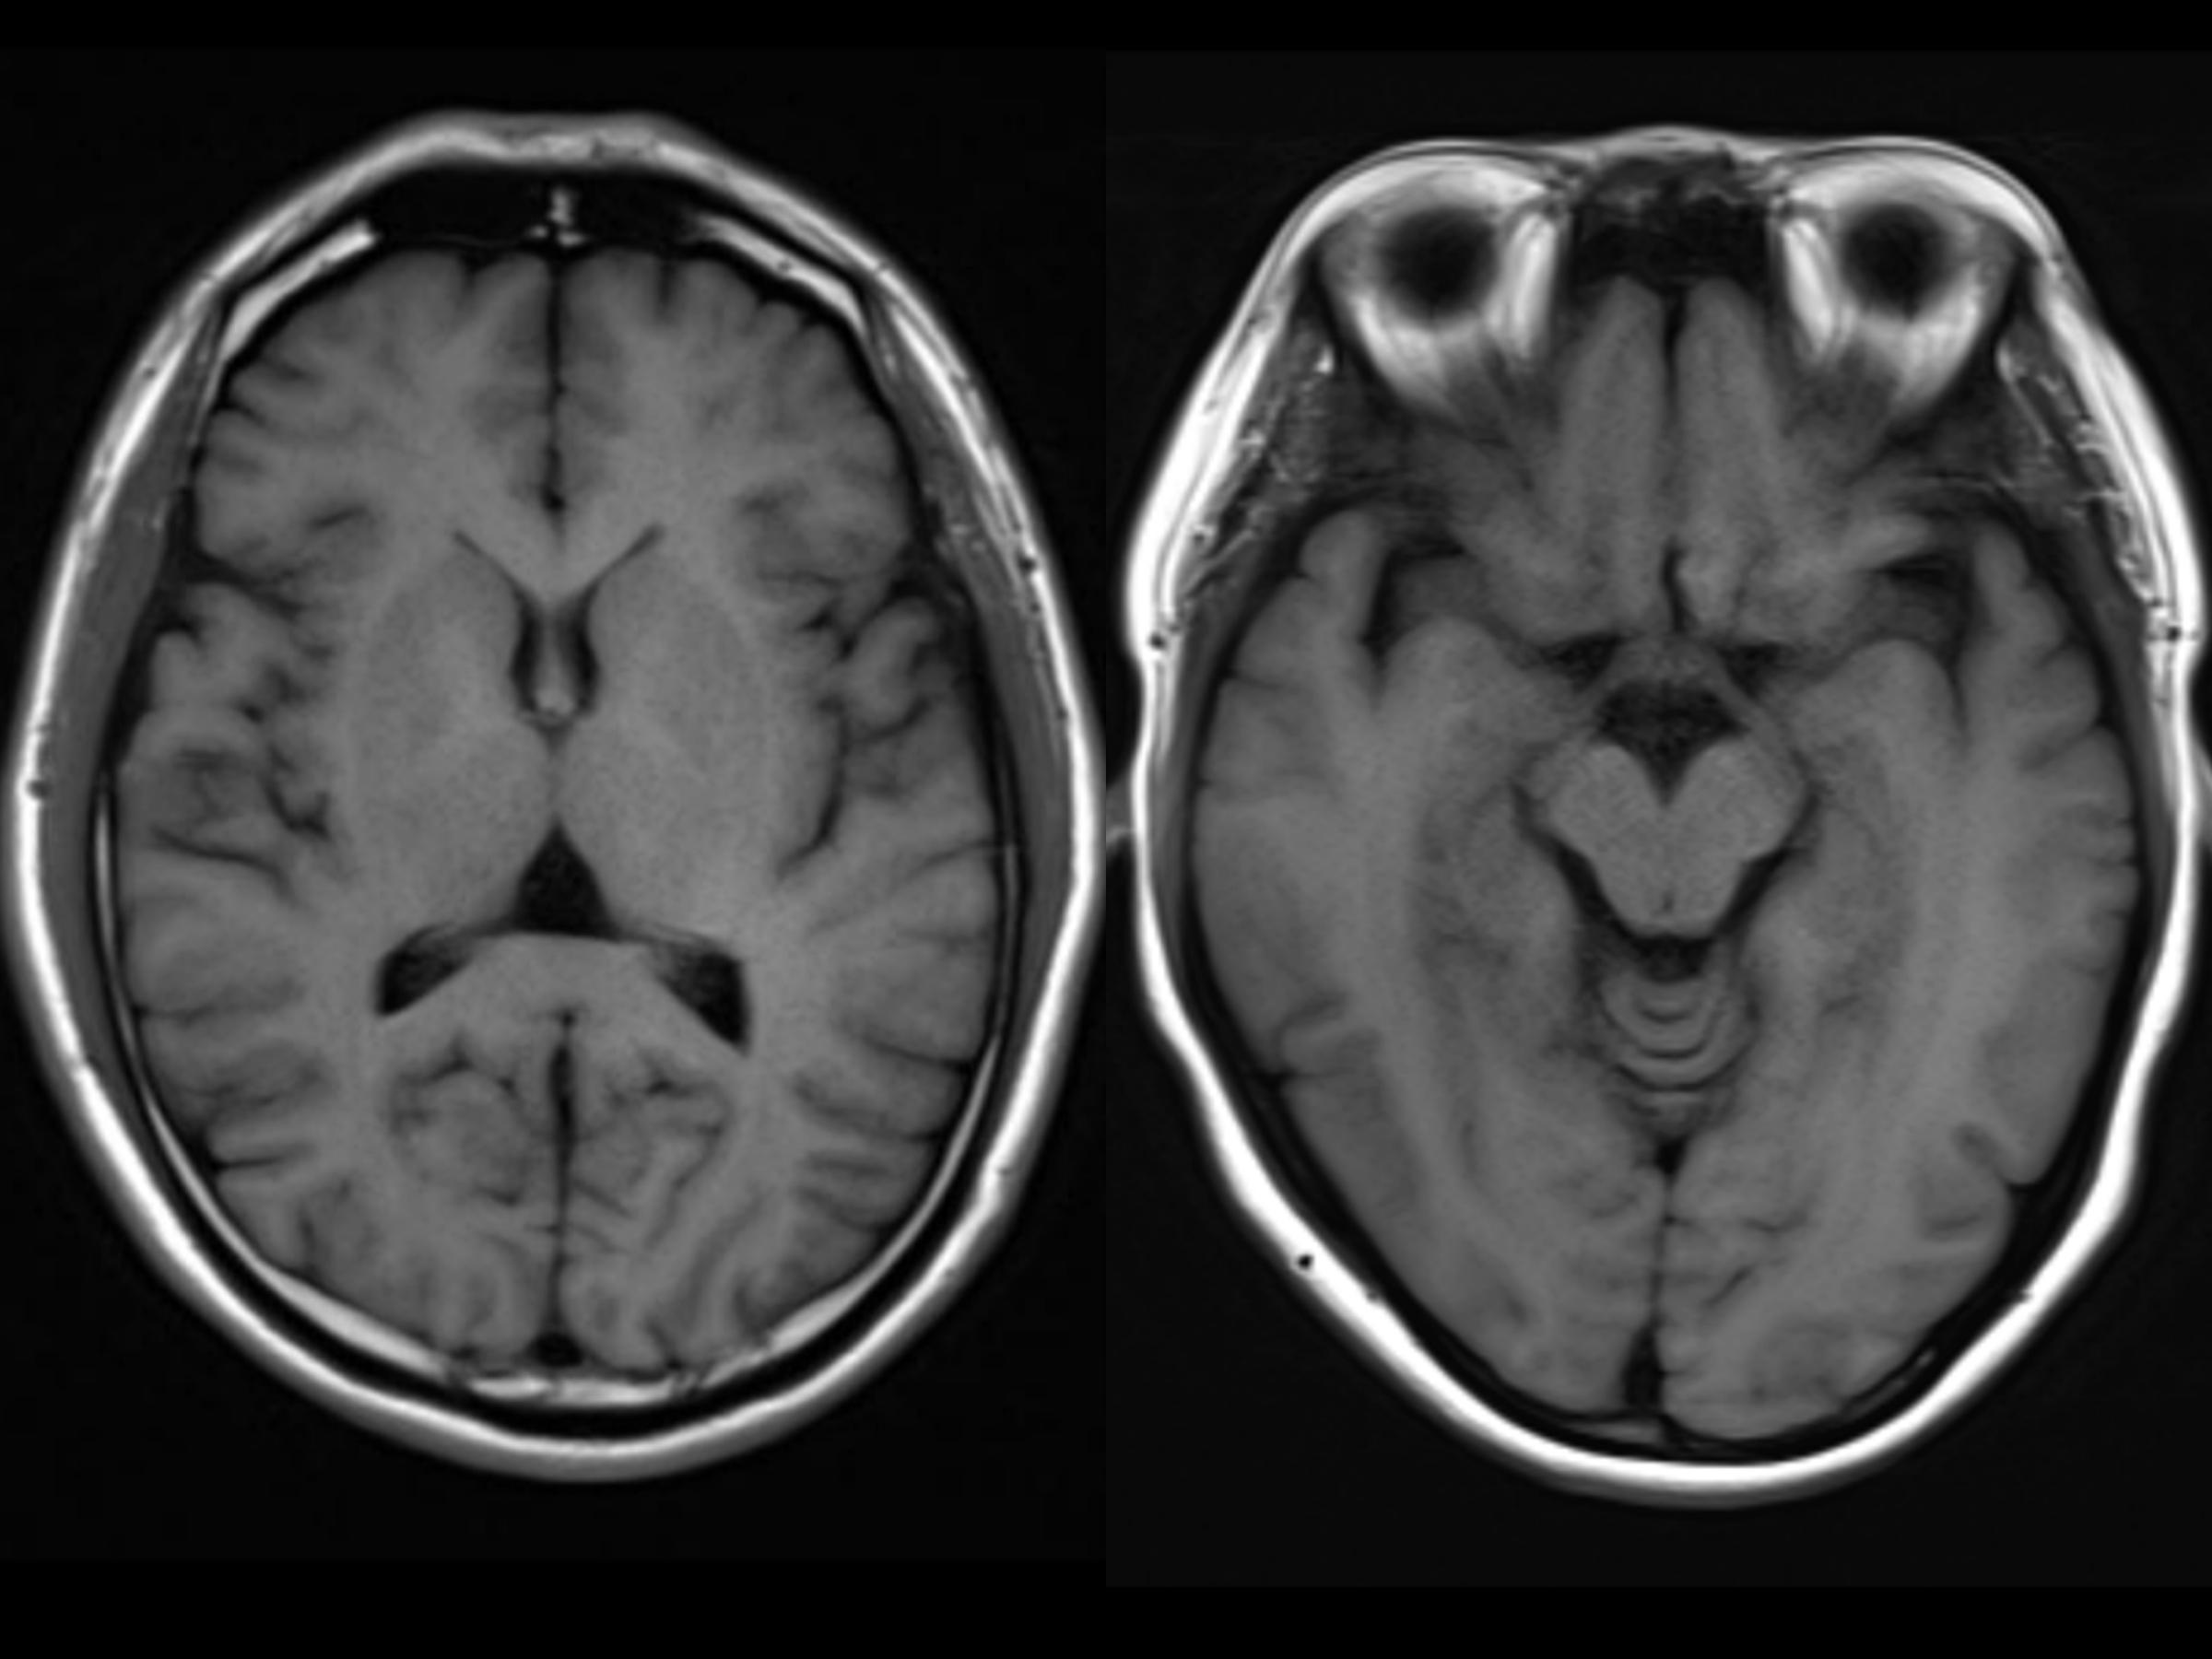

先来看看正常的大脑图像:

MRI检查正常的大脑